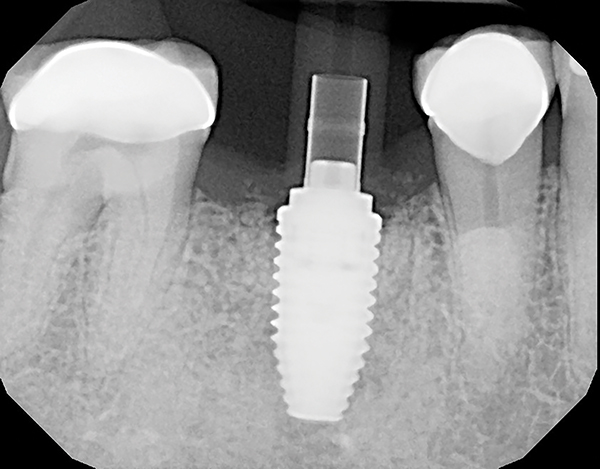

A mandibular right first molar was extracted due to an advanced Class III furcation and an irreversible pulpitis—a combination lesion. An immediate implant placement protocol was elected, and a PEEK abutment was placed on the implant (Figure 1). After 3 months of healing, a scan body was placed on the osseointegrated implant (Figure 2 and Figure 3), and an intraoral scan was taken (TRIOS Pod) (Figure 4) for the fabrication of a screw-retained crown.

Fig 4. Intraoral scanning with digital impression scanner.

Figure 4